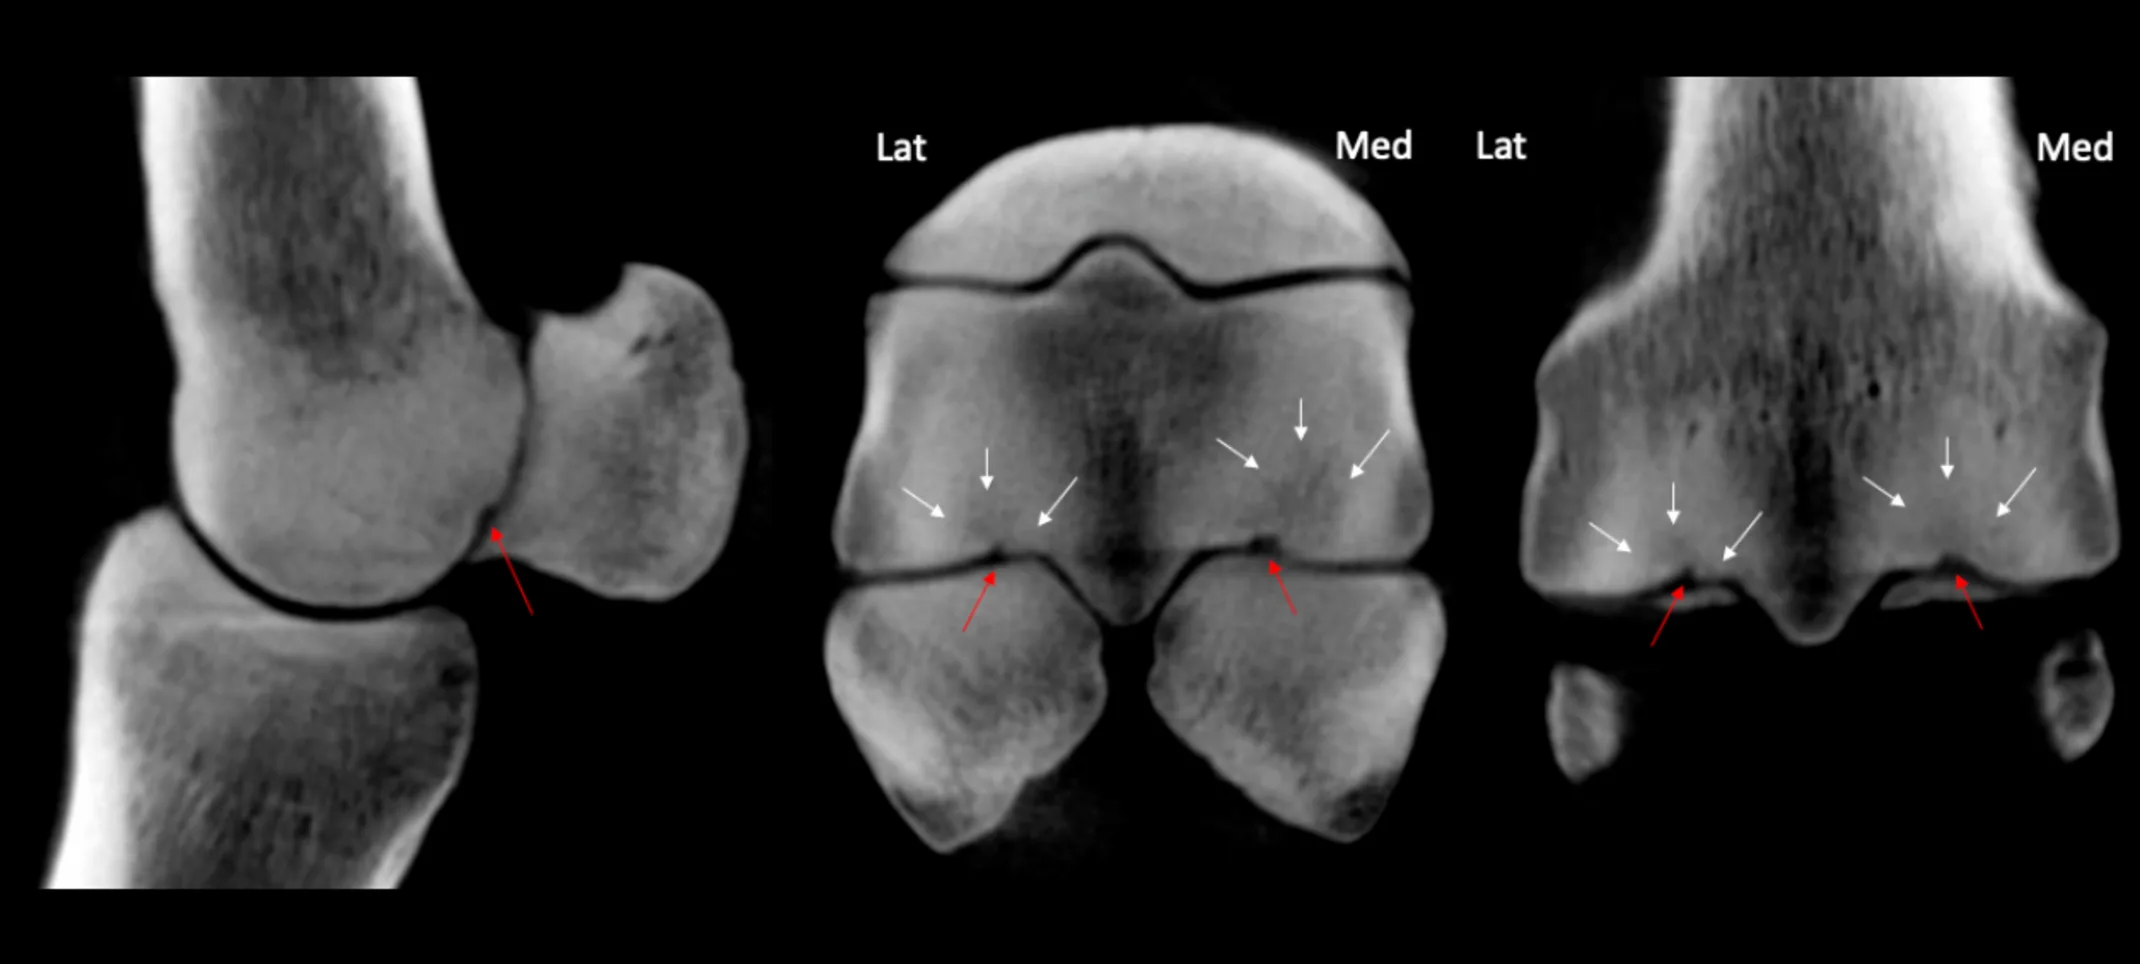

With a large population of horses being used for race, show and recreation throughout the mid-Atlantic, appropriate management of injuries and illness over the lifetime of the horse is a high priority for EVC. While there are many facets of equine medical management, readily available technologies such as digital radiology and ultrasound often lack diagnostic sensitivity whereas current hospital based advanced imaging systems require anesthesia or complex positioning that makes them impractical or inaccessible to many horses.

We anticipate installation of a standing CT system that will be the first of its kind in the US at the new EVC clinic in 2024. The goal is to safely image a sedated standing horse to detect pathology under natural load-bearing conditions with a scan time of about 20 seconds enabling screening for suspected/risk injuries. We believe standing CT will be a valuable addition to other measures in place to protect the safety and health of our horses here in the mid-Atlantic.